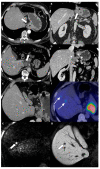

Gastric cancer (GC) is a common cancer worldwide. Its incidence and mortality vary depending on geographic area, with the highest rates in Asian countries, particularly in China, Japan, and South Korea. Accurate imaging staging has become crucial for the application of various treatment strategies, especially for curative treatments in early stages. Unfortunately, most GCs are still diagnosed at an advanced stage, with the peritoneum (61-80%), distant lymph nodes (44-50%), and liver (26-38%) as the most common metastatic locations. Metastatic disease is limited to the peritoneum in 58% of cases; in nonperitoneal distant metastases, the most involved GC metastasization site is the liver (82%). The eighth edition of the tumor-node-metastasis staging system is the most commonly used system for determining GC prognosis. Endoscopic ultrasonography, computed tomography, and 18-fluorideoxyglucose positron emission tomography are historically the most accurate imaging techniques for GC staging. However, studies have recently shown renewed interest in magnetic resonance imaging (MRI) as a useful tool in GC staging, especially for distant metastasis assessment. The technical improvement of diffusion-weighted imaging and the increasing use of hepatobiliary contrast agents have been shown to increase the diagnostic performance of MRI, particularly for detecting peritoneal and liver metastasis. However, no principal oncological guidelines have included the use of MRI as a first-line technique for distant metastasis evaluation during the GC staging process, such as the National Comprehensive Cancer Network Guidelines. This review analyzed the role of the principal imaging techniques in GC diagnosis and staging, focusing on the potential role of MRI, especially for assessing peritoneal and liver metastases.